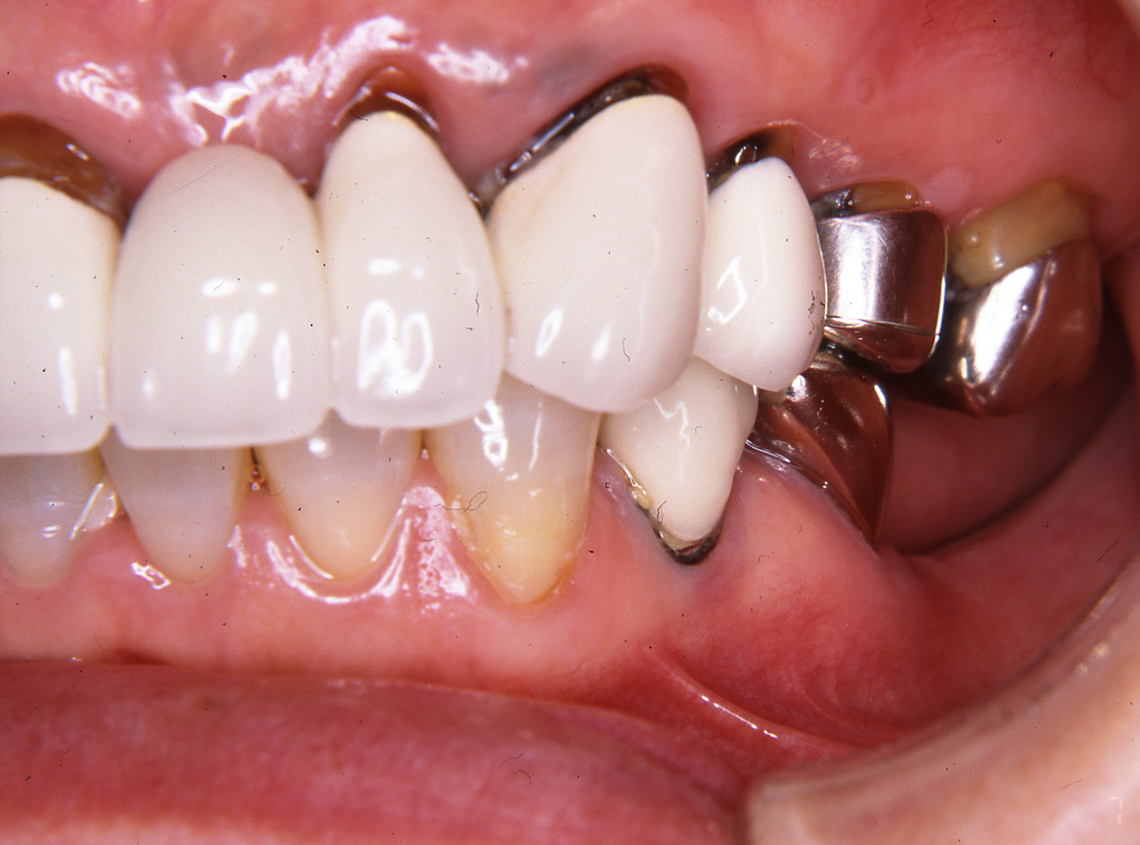

フルマウス治療17年間経過症例

患 者 : S.K様 女性

主 訴 : 補綴物破損、義歯不適による咀嚼障害のためインプラント治療希望

初診日 : 2003年07月11日

1.初診時(2003年)